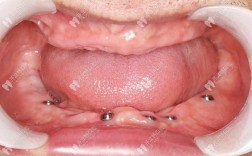

针对不同年龄段和错颌类型,医院正畸科室提供多元化的矫治方案选择,对于青少年患者,重点强调早期干预,通过功能性矫治器(如FRⅢ、Twin Block等)引导颌骨正常发育,降低后期复杂矫治的难度;对于成人患者,则更注重美观与功能的协调,除传统金属托槽矫治外,还提供陶瓷托槽、隐形矫治(如隐适美、时代天使)、舌侧矫治等美观性矫治方式,满足患者对“隐形”“美观”的需求,科室还特别关注唇腭裂、牙周病伴发错颌畸形等特殊病例的矫治,联合修复科、颌面外科等多学科团队,制定综合治疗方案,确保治疗效果。

牙齿正畸的治疗流程通常包括初诊检查、方案设计、矫治实施、保持四个阶段,初诊时,医生会通过临床检查、影像学检查(如X线头颅侧位片、曲面断层片)及数字化扫描等方式收集患者口腔数据;方案设计阶段,结合患者的主观需求与客观检查结果,制定个性化矫治计划,并通过3D动画向患者展示预期效果;矫治实施过程中,患者需定期复诊(通常为4-6周一次),医生根据牙齿移动情况调整矫治力;拆除矫治器后,需佩戴保持器以维持疗效,防止复发,整个治疗周期因错颌类型复杂程度不同,通常为1.5-3年,期间患者需与医生密切配合,注意口腔卫生维护,避免食用过硬、过黏食物。